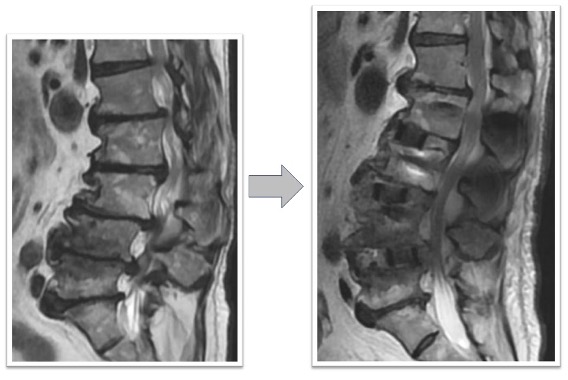

頚椎・腰椎の加齢変性による狭窄症やすべり症、椎間板ヘルニア、圧迫骨折など様々な脊椎脊髄疾患への手術治療を行います。術前画像シミュレーション、手術用顕微鏡、術中透視を用いて安全で確実な手術を常に心がけます。また低侵襲治療を心がけ、対象の疾患には顕微鏡や経皮的椎弓根スクリューを用いた小さな傷での治療を行います。執刀は全て手術経験豊富な専門医が行います。当院は脊椎手術に関しては2024年度345件、2025年も350件を超える手術件数(12月13日時点)と圏内トップクラスの手術件数となっています。特に重症の椎間板ヘルニアやすべり症、脊柱管狭窄に対して適応のあるOLIF(*LLIF(側方経路腰椎椎体間固定術)の変法)と呼ばれる新しい最小侵襲脊椎固定術の件数は2024年全国2位(*メーカー調べ)の161件で、2025年も200件に及ぶ治療を実施しており、日本国内トップレベルの手術件数です。

変性側弯を伴う多椎間の椎間板ヘルニア、脊柱管狭窄症(図3,4)

下肢痛、歩行障害、腰痛で来院、手術となりました。術前後のレントゲンで3椎間のOLIFによって術後側弯症が改善され、脊椎の並び(アライメント)が矯正されています(図3)。また、術前後のMRIでは施術した部位の椎間板ヘルニアおよび脊柱管狭窄がOLIFの間接除圧効果によって改善し、神経への圧迫が解除されています(図4)。術後は歩行可能、下肢痛腰痛も改善、また結果として数センチ身長が回復しています。

図3

図4